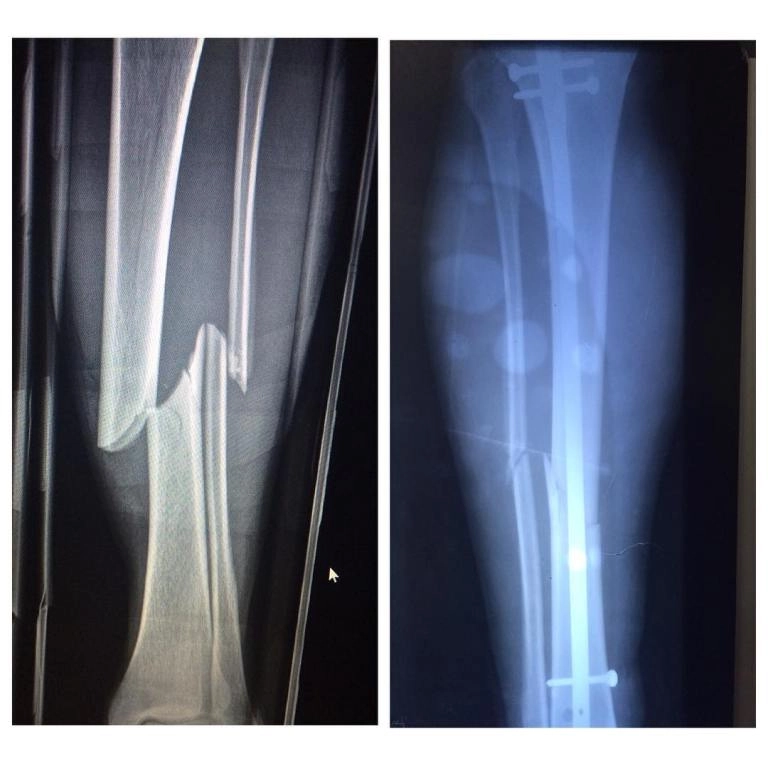

• Артроскопия проводится с использованием щадящих технологий, позволяющих лечить повреждения плечевого, коленного, локтевого

и голеностопного сустава с минимальной травматизацией.

• Для людей, столкнувшихся с повреждениями колена,

актуально будет лечение разрыва мениска.

Врач выполняет операции с учетом возраста пациента, уровня физической активности и индивидуальных особенностей организма.